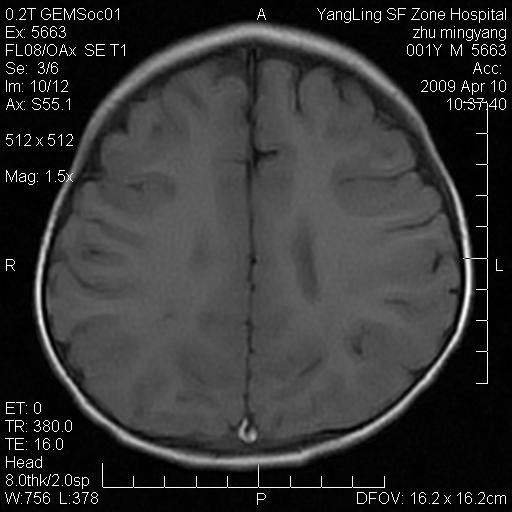

患者:1岁半,两天前外伤收住我院,ct检查小脑占位

考虑星形细胞瘤,建议增强

髓母细胞瘤或血管母细胞瘤,增强后可以鉴别;影像资料见 <。鱼博浪老师的《中枢神经系统ct与mr鉴别诊断》 小脑部肿瘤章节。

髓母细胞瘤或血管母细胞瘤!支持!

支持考虑髓母细胞瘤

考虑----髓母细胞瘤可能性大

考虑髓母细胞瘤或室管膜瘤。

支持髓母细胞瘤。

考虑髓母细胞瘤。

考虑髓母细胞瘤或星形细胞瘤

考虑髓母细胞瘤.

考虑髓母细胞瘤可能性大。

小脑肿瘤.考虑髓母细胞瘤可能.

就病灶部位及临床资料首先考虑髓母.